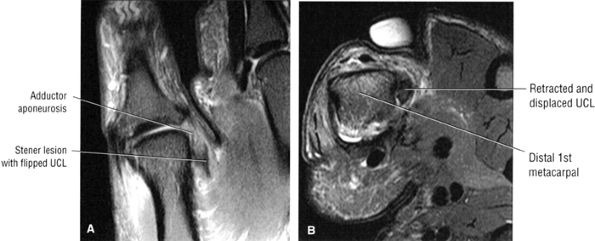

FIGURE 10.23 ● ADDUCTOR POLLICIS The adductor pollicis has two heads that converge into a tendon that inserts, along with fibers from the adjacent flexor pollicis brevis, onto the ulnar side of the base of the first phalanx of the thumb. There is a sesamoid bone present in the tendon. In tears of the ulnar collateral ligament of the thumb (gamekeeper's thumb), the adductor pollicis aponeurosis can interpose between the torn ulnar collateral ligament and the thumb, precluding healing (Stener's lesion). Stener's lesions must be surgically corrected to prevent persistent instability of the metacarpophalangeal joint.

![]() |